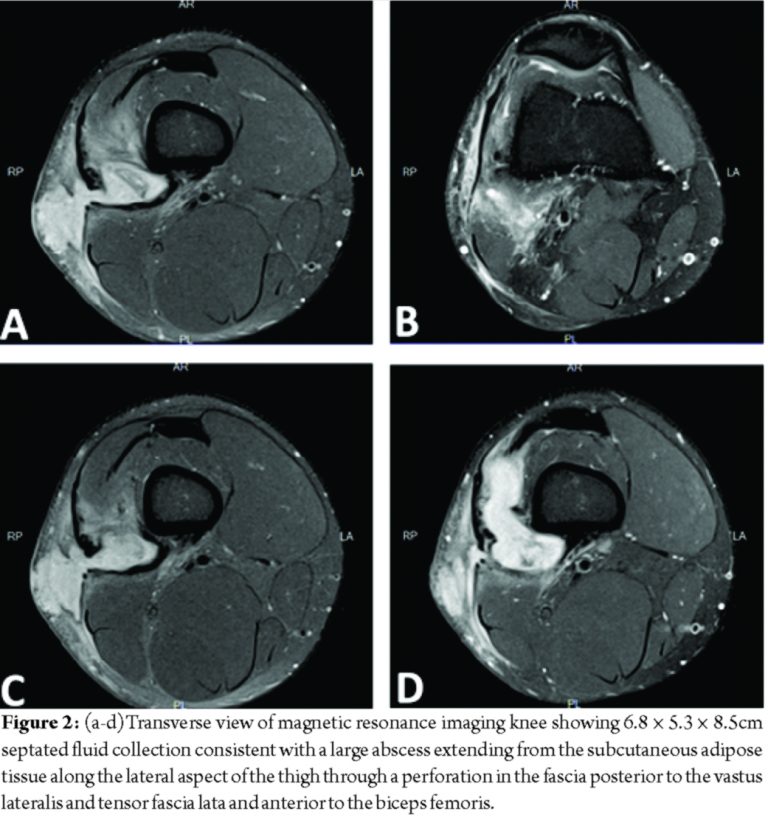

At presentation, the patient stated that this episode did not resolve with rest or anti-inflammatory medication. He reported the drainage had been ongoing for 2 weeks and appeared to come from a punctum in the center of the swelling, but denied any fever, chills, sharp pain, change in sensation, or restriction in active or passive range of motion. X-ray showed no acute OM or fractures (Fig. 1a and b). Magnetic resonance imaging (MRI) of the knee revealed 6.8 × 5.3 × 8.5cm septated fluid collection consistent with a large abscess extending from the subcutaneous adipose tissue along the lateral aspect of the thigh through a perforation in the fascia posterior to the vastus lateralis and tensor fascia lata and anterior to the biceps femoris (Fig. 2a-d). The fluid collection also extended deep between the muscle bellies to the level of the posterior lateral cortex of the distal femoral diaphysis. Diffuse soft-tissue edema was visualized; however, no periosteal or marrow edema was present, confirming the absence of acute OM (Fig. 3a and b).